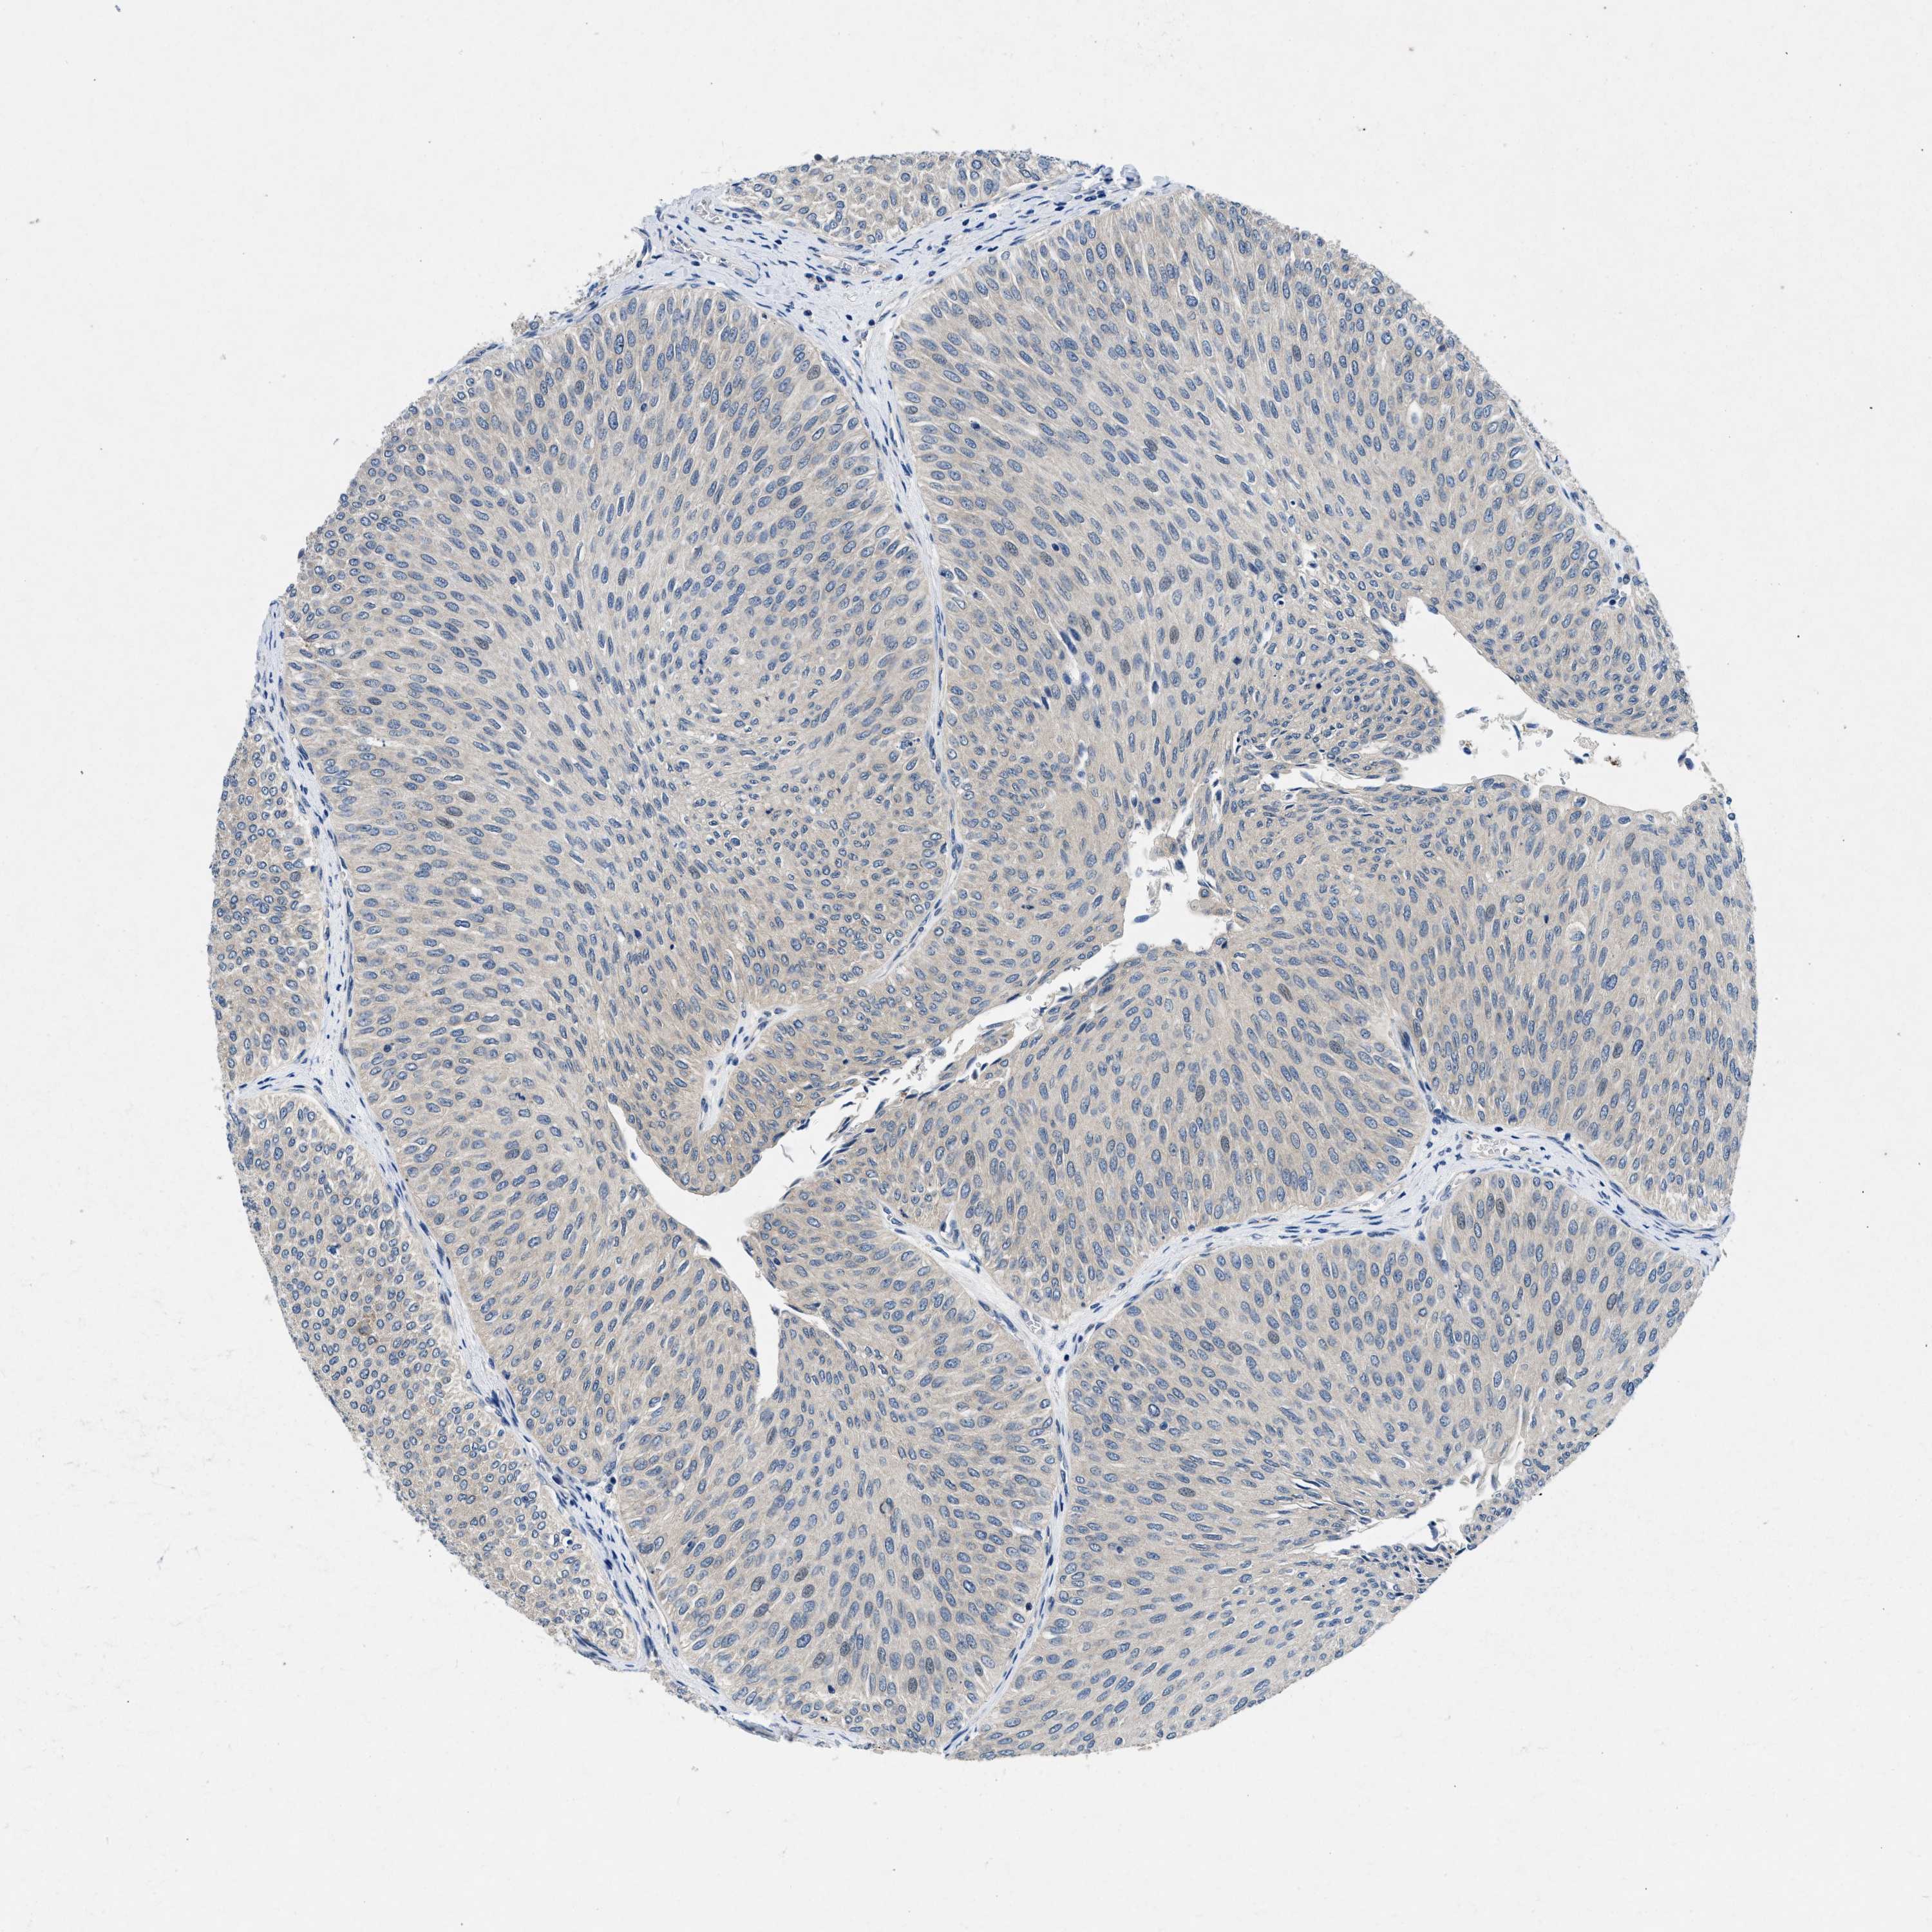

UROTHELIAL CANCER - Protein expressioni

A mouse-over function shows sample information and annotation data. Click on an image to view it in a full screen mode. Samples can be filtered based on level of antibody staining by selecting one or several of the following categories: high, medium, low and not detected. The assay and annotation is described here.

Antibody stainingi

Antibody staining in the annotated cell types in the current human tissue is reported as not detected, low, medium, or high, based on conventional immunohistochemistry profiling in selected tissues. This score is based on the combination of the staining intensity and fraction of stained cells.

Each image is clickable and will lead to virtual microscopy that enables deeper exploration of all samples and also displays staining intensity scores, fraction scores and subcellular localization as well as patient and tissue information for each sample.

Antibody HPA016867

Urothelial carcinoma, Low grade

Urothelial carcinoma, High grade